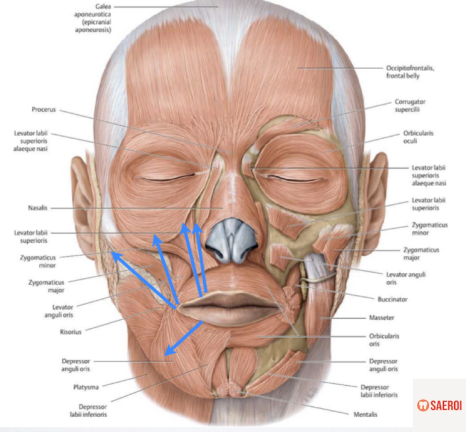

(2) 입술 주변 근육의 과도한 활성

입술 주변에는

우리가 웃을 때 미소를 짓게 만들어 주는

여러 근육들이 존재합니다.

이러한 근육들이 과도하게 활성화되는 경우,

즉, 웃을 때 입꼬리와 입술을 위로 올리는 근육이

너무 과하게 위로 당기는 힘을 주게 되면

커튼이 위로 올라가듯이

그 아래의 잇몸이 과하게 보이게 됩니다.

(2) 보톡스(botox)

여러 얼굴의 주름을 개선하기 위해 사용되는 보톡스는

보톨리늄 톡신을 피하 근육에 주입하여

근육의 활성을 억제하는 방법을 말합니다.

이러한 작용 기전을

입 주변 얼굴 근육에 적용하게 되면

과도한 움직임을 보이는 입술 올림 근육들의

과활성을 억제하게 됩니다.

미소 시 작용해야 하는 근육들을 억지로 마비시키는 방법이다 보니

웃을 때 약간 어색하게 보일 수 있다는 단점이 있습니다.

또한 보톡스의 작용 기간이 수개월 정도로 짧기 때문에

주기적인 시술이 필요하다는 단점도 존재합니다.